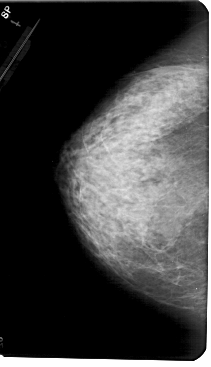

A_1985_1.LEFT_CC

LEFT_CC LINES 5491 PIXELS_PER_LINE 3151 BITS_PER_PIXEL 12 RESOLUTION 43.5 NON_OVERLAY